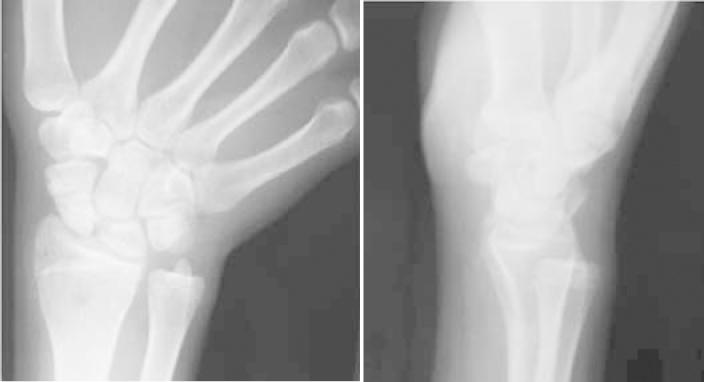

PSEUDARTHROSIS OF THE SCAPHOID IN IMMATURE SKELETONS.

This paper presents a review of the literature on pseudarthrosis of the scaphoid in skeletally immature individuals, taking into consideration its epidemiology, diagnosis and treatment, as well as its controversies. Knowledge of this subject makes it possible for patients to be given appropriate treatment immediately. Pseudarthrosis of the scaphoid in skeletally immature patients is a rare condition that results from error or lack of diagnosis of a fracture. Thus, careful clinical and radiographic examination should be performed in order to confirm or rule out this diagnosis. Several treatment methods have been reported and have shown good results. These include conservative plaster cast treatment, bone graft without osteosynthesis, bone graft with Kirschner wires, percutaneous screws and bone graft with compression screws. The treatment performed depends on the characteristics of the pseudarthrosis and the surgeon's experience.